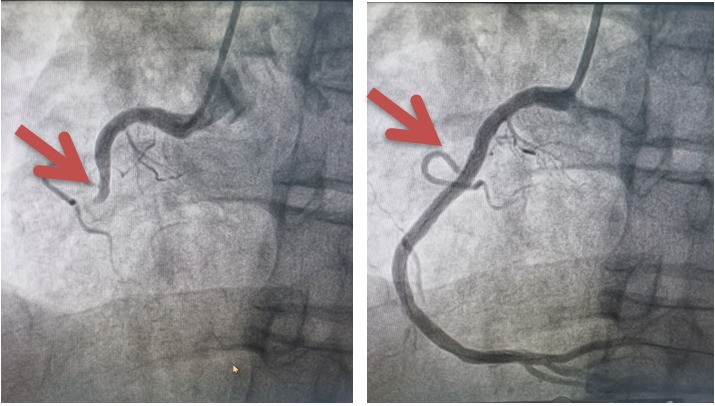

Khi vào Bệnh viện Hữu nghị Việt Tiệp, người bệnh nhanh chóng được tiến hành chụp mạch vành qua da chẩn đoán nhồi máu cơ tim cấp, tổn thương thân chung động mạch vành trái (vị trí hết sức nguy hiểm là nơi ngã ba của 2 mạch máu lớn nuôi quả tim) có tình trạng sốc tim đe doạ tính mạng.

Người bệnh đã được Khoa Can thiệp Tim và Mạch máu cùng cộng sự đã đặt stent động mạch vành. Nhờ được can thiệp cấp cứu kịp thời mà người bệnh đã thoát khỏi giai đoạn nguy hiểm. Sau đặt stent động vành, tình trạng của người bệnh được cải thiện dần.

| Hình ảnh trước và sau tái lưu thông thân chung động mạch vành trái |